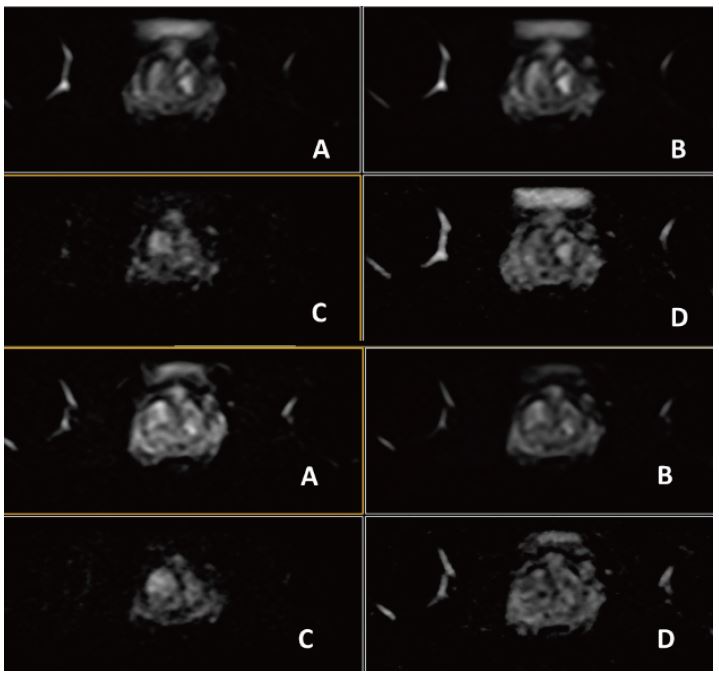

Рис. 4. Динаміка. Аксіал (12 фаз) : A=1a phase pre, B=3a phase pos, C=6a phase pos, D=12a phase (згідно протоколу m pMR)

Рис. 8. Динаміка. Аксіал (12 фаз): A=1a phase pre, B=3a phase pos, C=6a phase pos, D=12a phase (за протоколом mpMR) .

Рис. 12. Динаміка. Аксіал (12 фаз) : A=1a phase pre, B=3a phase pos, C=6a phase pos, D=12a phase (згідно протоколу m pMR)

Рис. 16.  Динаіка. Аксіал (12 фаз)– A=1a phase pre, B=3a phase pos, C=6a phase pos, D=12a phase (за протоколом mpRM).